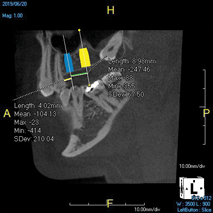

(7.) Treatment planning an implant case is made easier and more accurate by virtually placing implants of the chosen length and diameter and measuring the desired mesiodistal spacing prior to surgery.

Figure 7